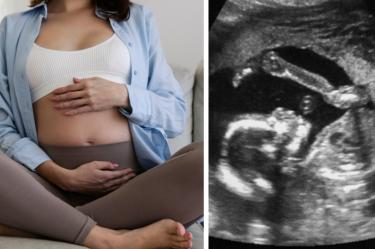

Si estás esperando a tu bebé, mejor que conozcas cuáles son las enfermedades que puede pasar la madre al feto y cómo prevenirlas para que estén los dos a salvo.

Es sabido que el embarazo es un estado delicado para muchas mujeres, pero ¿sabes cuáles son las enfermedades que pueden pasar de la madre al feto? Esta es la forma de evitarlas.

Durante el embarazo, se realizan controles médicos regulares que incluyen exámenes físicos, análisis de sangre, ultrasonidos y otros estudios para evaluar la salud tanto de la madre como del feto. Estos exámenes ayudan a monitorear el crecimiento y desarrollo del bebé, detectar cualquier problema potencial y garantizar que el embarazo progrese de manera saludable.